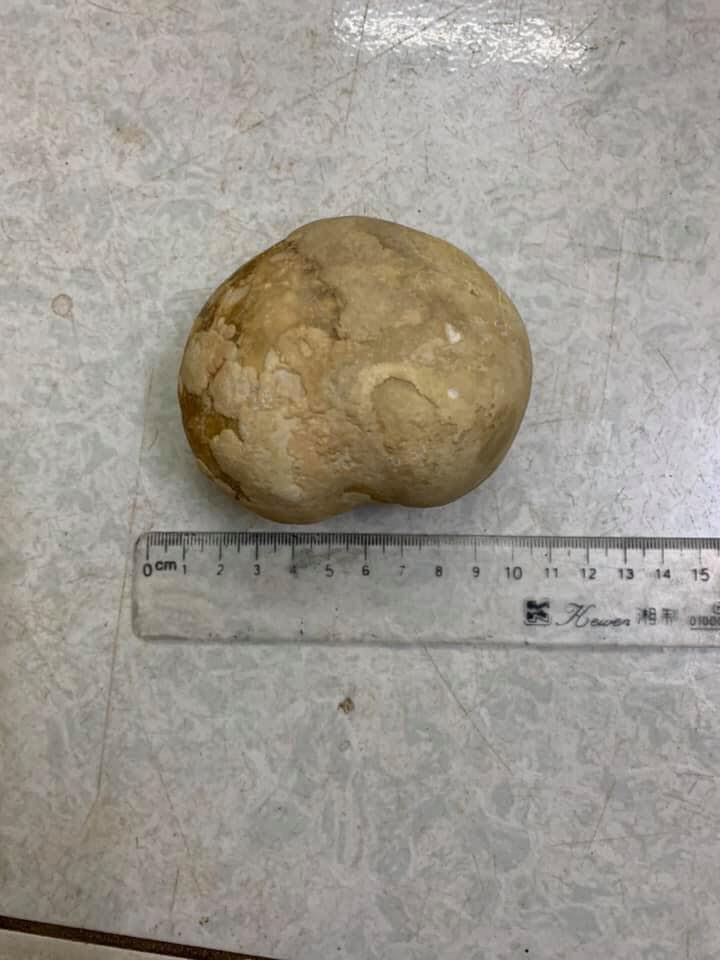

Photos of a giant bladder stone that a young woman recently had surgically removed have doing the rounds on Vietnamese social media.

Several Vietnamese media outlets have been reporting on the case of a 34-year-old woman who showed up at the emergency room of Phu Binh General Hospital, in Thay Nguyen, complaining of severe pain in her abdomen. After running some tests, a CT scan revealed that the woman had a massive, round mass in her abdomen. She was scheduled for emergency surgery, and a stone over 10-cm-long and weighing 400 grams was extracted from her bladder.

The news reports don’t offer too much information about this case, but photos include a CT scan, as well as a medical nurse posing with the giant stone. It was obviously quite a rare sight at the hospital…

According to a 2014 case report in the Turkish Journal of Urology, giant vesical calculi weighing more than 100 gm are rare, with fewer than 85 cases reported in English over the years involving a stone over 100 grams. If confirmed, this 400-gram- stone definitely qualifies as a medical oddity.

This is far from the largest bladder stone ever recorded. Back in 2016, Chinese doctors reported the case of a 54-year-old man who had a massive 1,048-gram pelvic stone in his bladder. And that was only the largest bladder stone ever recorded in China.

Photos of the 34-year-old woman’s 400-gram bladder stone went viral in Vietnam over the last couple of days, with most users expressing their disbelief about the woman’s threshold for pain.